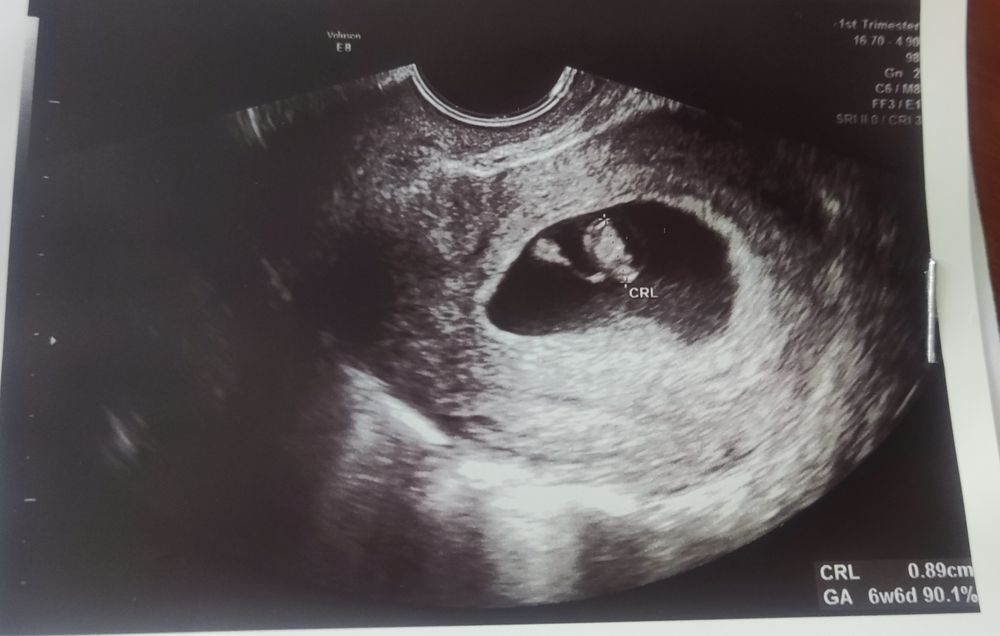

Первое УЗИ в 6.6 недель ❤️❤️❤️

Беременность- 1 триместр ( только до 10 недель)Вот я и сходила на первое УЗИ. Не дотерпела до 8 недель. Думала, что сегодня ровно 7 недель, а оказалось, что 6.6. Посмотрела на малышарика, послушала сердечко и так спокойно и радостно стало.

Кто там разбирается все норм по срокам, числам? Узист сказала, что все по срокам. Но почему пя на 7.5 недель, а эмбрион на 6.6. Ну вроде ему там места хватает, это ж хорошо?)) Просто интересно он позже появился? И вообще от чего зависит как быстро эмбриончик появляется? Теперь запишусь в ЖК и буду ждать скрининга. Всем хочушкам долгожданной беременности здоровой, а всем беременным-здоровых деток и родов в срок❤️